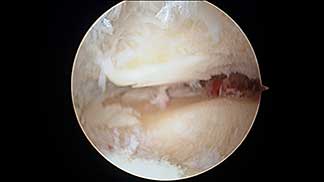

• • Lesiones De Meniscos

Según el tejido afectado y la profundidad o intensidad de la lesión pueden ser: cutáneas (de la piel), musculares; rotura de fibras, desgarres, distensiones o esguinces.

Ligamentosas o ligamentarias con distensiones y rupturas totales o parciales.